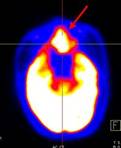

Ca lâm sàng 1: Bệnh nhân Vũ D.L., nam, 56 tuổi. Chẩn đoán: Non-Hodgkin Lymphoma , GPB: WF7.

Hình PET/CT toàn thân thấy tổn thương hạch ở nhiều vị trí: vùng cổ, trung thất, hố nách, ổ bụng, bẹn (các mũi tên)